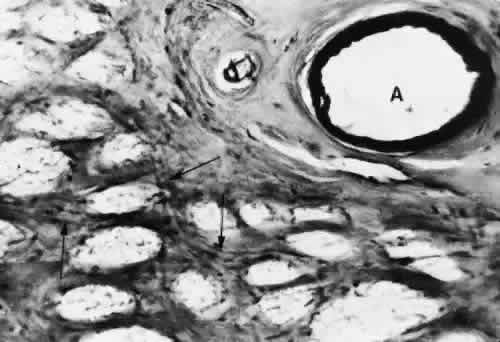

In the retrolaminar zone, the contribution of the choroidal vessels is less. The peripheral aspects of the postlaminar optic nerve are supplied by the pial vessels, whereas the central portion is fed by the axial vessels off the CRA. The afferent channels derived from the short PCAs that cross the border tissue of Elschnig at the level of the choroid have a diameter ranging from 10 to 17 μm.36,37 They quickly branch into a tridimensional vascular network with a polygonal capillary bed. The capillary bed is nonfenestrated, with tight junctions. Numerous pericytes surround the endothelial cells. The capillary mesh measures from30 × 50 μm to 50 × 80 μm, and there are multiple arterial feeding points into the meshwork. The density of the meshwork seems equal in all disc quadrants. Although the capillary bed of the optic nerve head is derived mostly from posterior ciliary vessels, it more closely resembles the retinal capillary bed morphologically than the choriocapillaris. The major efferent vessel for this area of the optic nerve is the CRV. Some of the prelaminar drainage may be through the choroid as well. Direct communications between the CRV and choroidal veins may exist as a result of CRV obstruction or as anatomical variants, which would make the eventual drainage system the vortex veins. The surface capillaries of the optic disc are derived from the retinal vessels.35,37 They anastomose with capillaries of the retina. The prelaminar, choroidal-derived vessels may contribute somewhat to the surface capillary supply. The postcapillary venules that drain the RPC system cross over the disc margin to join with larger venules of the CRV system. It may be these terminal endings of the RPC that bleed with papilledema and other causes of disc swelling. The blood flow to the optic nerve head appears to be under local autoregulatory control.38–40 This flow pattern is similar to the retinal circulation. The site of the autoregulation is not clear; however, both endothelial cells and pericytes probably have a role. The clinical appearance of optic nerve blood vessels in various pathologic conditions has been the focus of intense interest. Alterations in optic nerve blood vessels associated with advancing glaucoma have been an area of particular study in light of the theories concerning a vascular origin for the disease. Quigley and colleagues41 noted that the density of optic nerve head capillaries did not appear to change with worsening glaucoma and that eventual loss of capillaries was in proportion to the accompanying loss of neural tissue. Jonas and associates42 showed that the diameter of parapapillary retinal blood vessels was smaller in eyes with advanced glaucoma than in eyes without glaucomatous damage. This finding appears to represent an autoregulatory response of the retinal and optic disc vasculature to the local loss of retinal ganglion cells and nerve fiber layer. This study confirms an earlier report showing a significant decrease of RBF to the retina in eyes that had undergone inner retinal degeneration.43 CHOROID The choroid is by far the most vascular portion of the eye and by weight is one of the most vascular tissues in the body.44 More than 80% of all ocular blood flow goes to the choroid. The choroidal circulation is responsible for the nourishment of the photoreceptor/retinal pigment epithelium (RPE) complex. Despite these facts, the choroidal circulation has received relatively little attention for two reasons. First, it is difficult to visualize the choroidal vessels directly, and second, there are relatively few pathologic conditions that have unequivocally been associated with a primary deficiency in choroidal circulation. Choroidal blood flow can be assessed in a qualitative manner with fluorescein angiography. The rapidity of choroidal filling, the normal permeability of the choriocapillaris, and the normal blockage of fluorescence as a result of the RPE impede the identification of choroidal perfusion defects. When present, the clinical significance of choroidal perfusion defects on fluorescein angiography is not always clear, either. Newer methods used to study choroidal perfusion more quantitatively include indocyanine green angiography and color Doppler ultrasonography.45,46 Indocyanine green angiography in particular has made the choroid more accessible to clinical evaluation and interpreting the role of the choroid in various disease entities. Along with its paramount task of providing nutrition to the outer retina and RPE, the choroidal circulation also has other roles. It serves as a heat sink, removing the large amount of heat that develops as a result of the metabolic processes initiated when photons strike the photopigments and RPE.47 In addition, the choroid itself probably serves as a mechanical cushion for the internal structures of the eye. The overall structure of the choroidal circulation is segmental.47–52 This segmental distribution of blood begins at the level of the posterior ciliary branches and is mirrored in the vortex vein drainage system. Because of the segmental distribution, the large and medium-sized choroidal arteries act as end arteries. Unlike most other tissues, in the choroid the large vessels do not run parallel to each other. The segmental distribution of blood flow to the choriocapillaris is reflected in certain disease states, such as malignant hypertension. Each terminal choroidal artery supplies an independent lobule of choroidal capillaries (Figs. 11 and 12). Examination of the lobular structure reveals that feeding arterioles are usually found in the lobule center with draining venules located at the lobular periphery, but reversals of this pattern are frequently seen. There is little or no functional communication between adjacent capillary lobules.53–56 The vasculature of the choroid appears to be under direct adrenergic innervation.13,57 It is hypothesized that the parasympathetic innervation is through the seventh cranial nerve by way of the pterygopalatine ganglion.58 Arteries and Arterioles Within the choroid, the arteries and arterioles lie in stratified layers, with the larger vessels located in the outermost layer. The innermost layer of choroidal vessels is a single layer of capillaries. The arteries of the choroid measure between 20 and 90 μm in diameter.59 The larger vessels contain an endothelium and basement membrane, an internal elastic membrane, and a single continuous layer of smooth muscle cells. The muscle cells contain abundant myofilaments, and pinocytotic vesicles are arranged along the inner surface of the plasma membrane. The adventitia is composed of bundles of collagen fibers, scattered elastic fibers, and occasional fibroblasts. In the smaller vessels (arterioles), the internal elastic membrane disappears, and the muscle layer becomes discontinuous and more circumferentially arranged. The collagen present in the adventitia also becomes considerably diminished. Veins and Venules The choroidal veins that directly feed the vortex veins have a diameter less than 150 μm.59 The veins with a diameter between 50 and 150 μm have an endothelium and basement membrane with one or two layers of smooth muscle and a relatively thick collagenous adventitia. In the venules (smaller than 40 μm), the intima is the same, but the media contains a discontinuous layer of longitudinally arranged pericytes. Choriocapillaris The choriocapillaris is the unique capillary system of the choroid. The vessels of the choriocapillaris are unusual because of their large diameters. The lumina are typically larger than 8 μm. Lumina of this size allow passage of multiple red blood cells at any moment in time. The choriocapillaris is arranged in a specific lobular pattern to ensure maximum exposure of the overlying outer retina/RPE complex. Each lobule acts as an independent vascular system with its own afferent and efferent vessels.60 Within the posterior pole region, there are more venules than arterioles, probably to allow rapid flow. Other local variations exist. The lobules at the posterior pole are 200 to 400 μm in diameter and gradually enlarge to 1,500 μm in the periphery and somewhat lose their lobular pattern (Fig. 13).54,61 The vessel walls themselves consist of fenestrated endothelium surrounded by a basement membrane and a sparsely arranged layer of pericytes. The portion of the endothelial cell containing the nucleus also contains most of the cell's cytoplasm and organelles. The remainder of the cytoplasm is extremely attenuated, and these regions contain the fenestrae. These fenestrae are approximately 700 to 800 nm in diameter and are covered by a diaphragm. The attenuated areas are most typically found facing the RPE and contain very few pinocytotic vesicles. The region of the cell facing the suprachoroidal space usually contains more cytoplasm, fewer fenestrae, and the nucleus (Fig. 14). Few pericytic processes are seen in cross sections of these vessels on the side of the vessel facing the pigmented epithelium (Fig. 15). However, these processes are more numerous on the surface of the vessel facing the sclera. Because of the fenestrae, the choriocapillaris actively leaks fluorescein molecules.